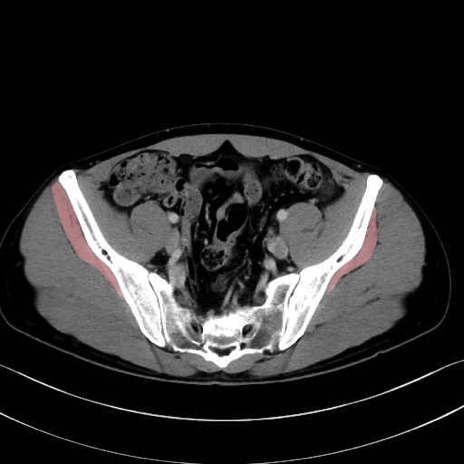

小殿筋 (Gluteus minimus)